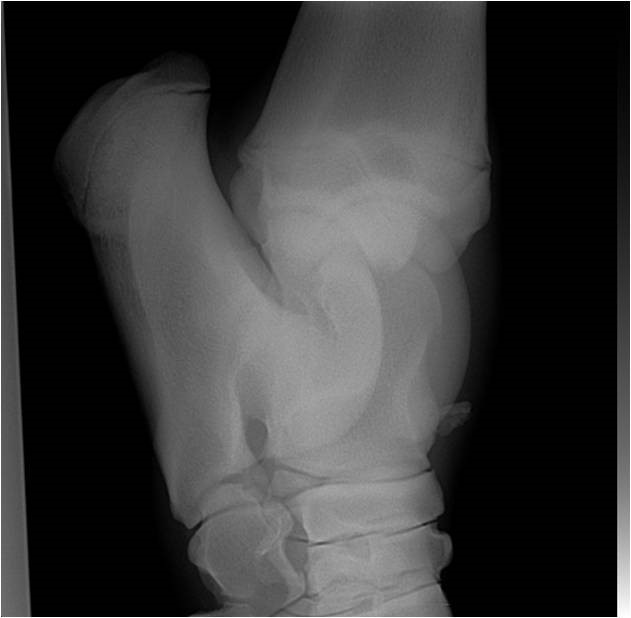

RöntgenZehe